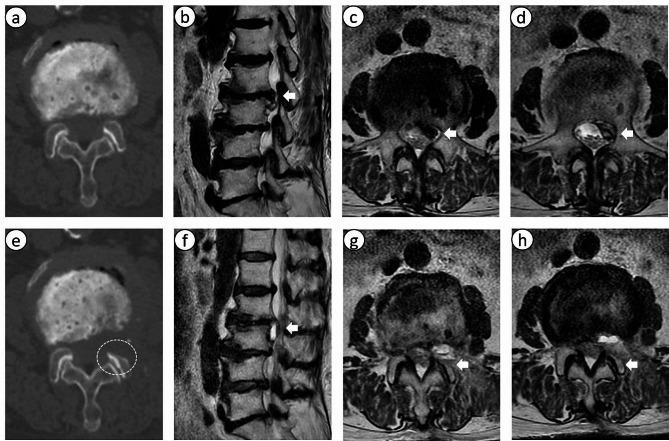

https://cdn.ncbi.nlm.nih.gov/pmc/blobs/afea/11179340/0925f7cc501f/12891_2024_7588_Fig2_HTML.jpg

https://cdn.ncbi.nlm.nih.gov/pmc/blobs/afea/11179340/f2539ff74cda/12891_2024_7588_Fig1_HTML.jpg